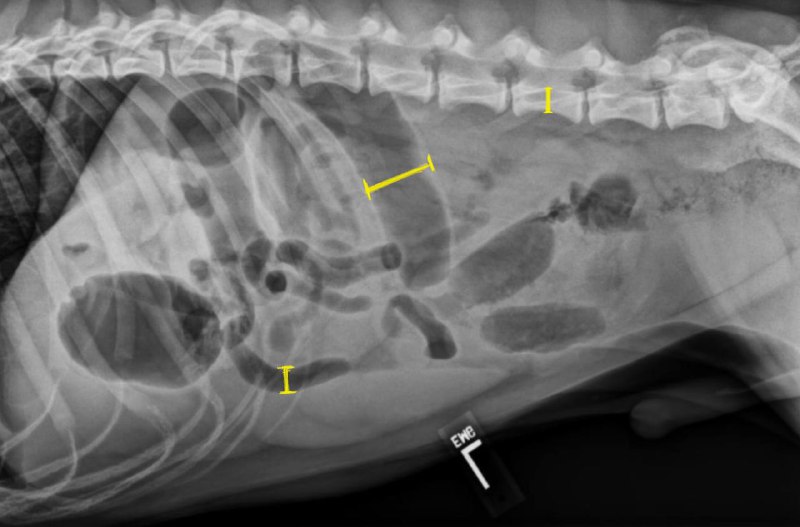

نسبت قطر روده کوچک به ارتفاع میانی مهره کمری پنجمL5

✅همه ی انسداد های روده ای نیاز به جراحی ندارند

✅یکی از راه های تشخیص این مورد(نیاز به جراحی) استفاده از این نسبت است

✅اگر نسبت قطر روده کوچک به ارتفاع L5 بیشتر از ۱.۶ شود احتمال انسداد وجود دارد

✅در رادیو گراف های سریالی اگر این نسبت رو به کاهش باشد معمولا نیاز به جراحی نیست ولی اگر افزایشی باشد معمولا کار به جراحی میکشد

✅اتساع روده کوچک ممکن است نمایی شبیه به کولون ایجاد کند برای تفریق آن می توان از انمای ماده حاجب استفاده کرد

❌اجسام خارجی خطی مانند نخ و طناب و … معمولا خطرناک تر بوده و تقریبا همیشه نیاز به جراحی دارند